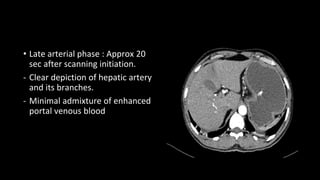

• Late arterial phase : Approx 20

sec after scanning initiation.

- Clear depiction of hepatic artery

and its branches.

- Minimal admixture of enhanced

portal venous blood

• Late arterialphase : Approx 20 sec after scanning initiation. - Clear depiction of hepatic artery and its branches. - Minimal admixture of enhanced portal venous blood